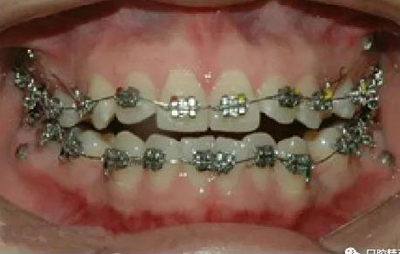

微型種植釘直徑僅有1.6mm和2mm,植入部位幾乎可以不受限制,可植入牙槽骨的任何部位,微型種植體支抗植入手術(shù)操作簡單、安全,不需要牙齦翻瓣,即可旋入微型種植體,整個(gè)手術(shù)過程僅需5-10min,術(shù)后患者的不良反應(yīng)少,微型種植體的取出亦非常簡單,甚至不需局部麻醉,將其反向旋出即可。自攻型種植釘植入牙槽骨中起支抗作用.

一般情況下是成年人使用,特殊病例十三、四歲的小孩可以用。種植釘可以打在牙槽骨的任何部位??梢栽?個(gè)牙齒之間的牙槽骨上打釘,或者打在頰側(cè)牙槽骨與牙根之間,主要看你是如何應(yīng)用支抗了。2個(gè)牙齒之間的牙槽骨上打釘,支抗作用拉動(dòng)的牙齒有限,而打在頰側(cè)牙槽骨與牙根之間可以將整個(gè)牙列拉向遠(yuǎn)中移動(dòng)。種植支抗釘在矯正結(jié)束后要拿下來。

2、助攻型種植釘,上頜與頜骨成30-40°角,下頜與頜骨成10-20°角(目的:1、降低損傷牙根及牙周膜的機(jī)率;2、使種植釘盡量植入骨皮質(zhì)內(nèi),降低松動(dòng)機(jī)率);自攻型種植釘與頜骨垂直;個(gè)人習(xí)慣:自攻型種植釘上下頜均與頜骨成30-40°角。